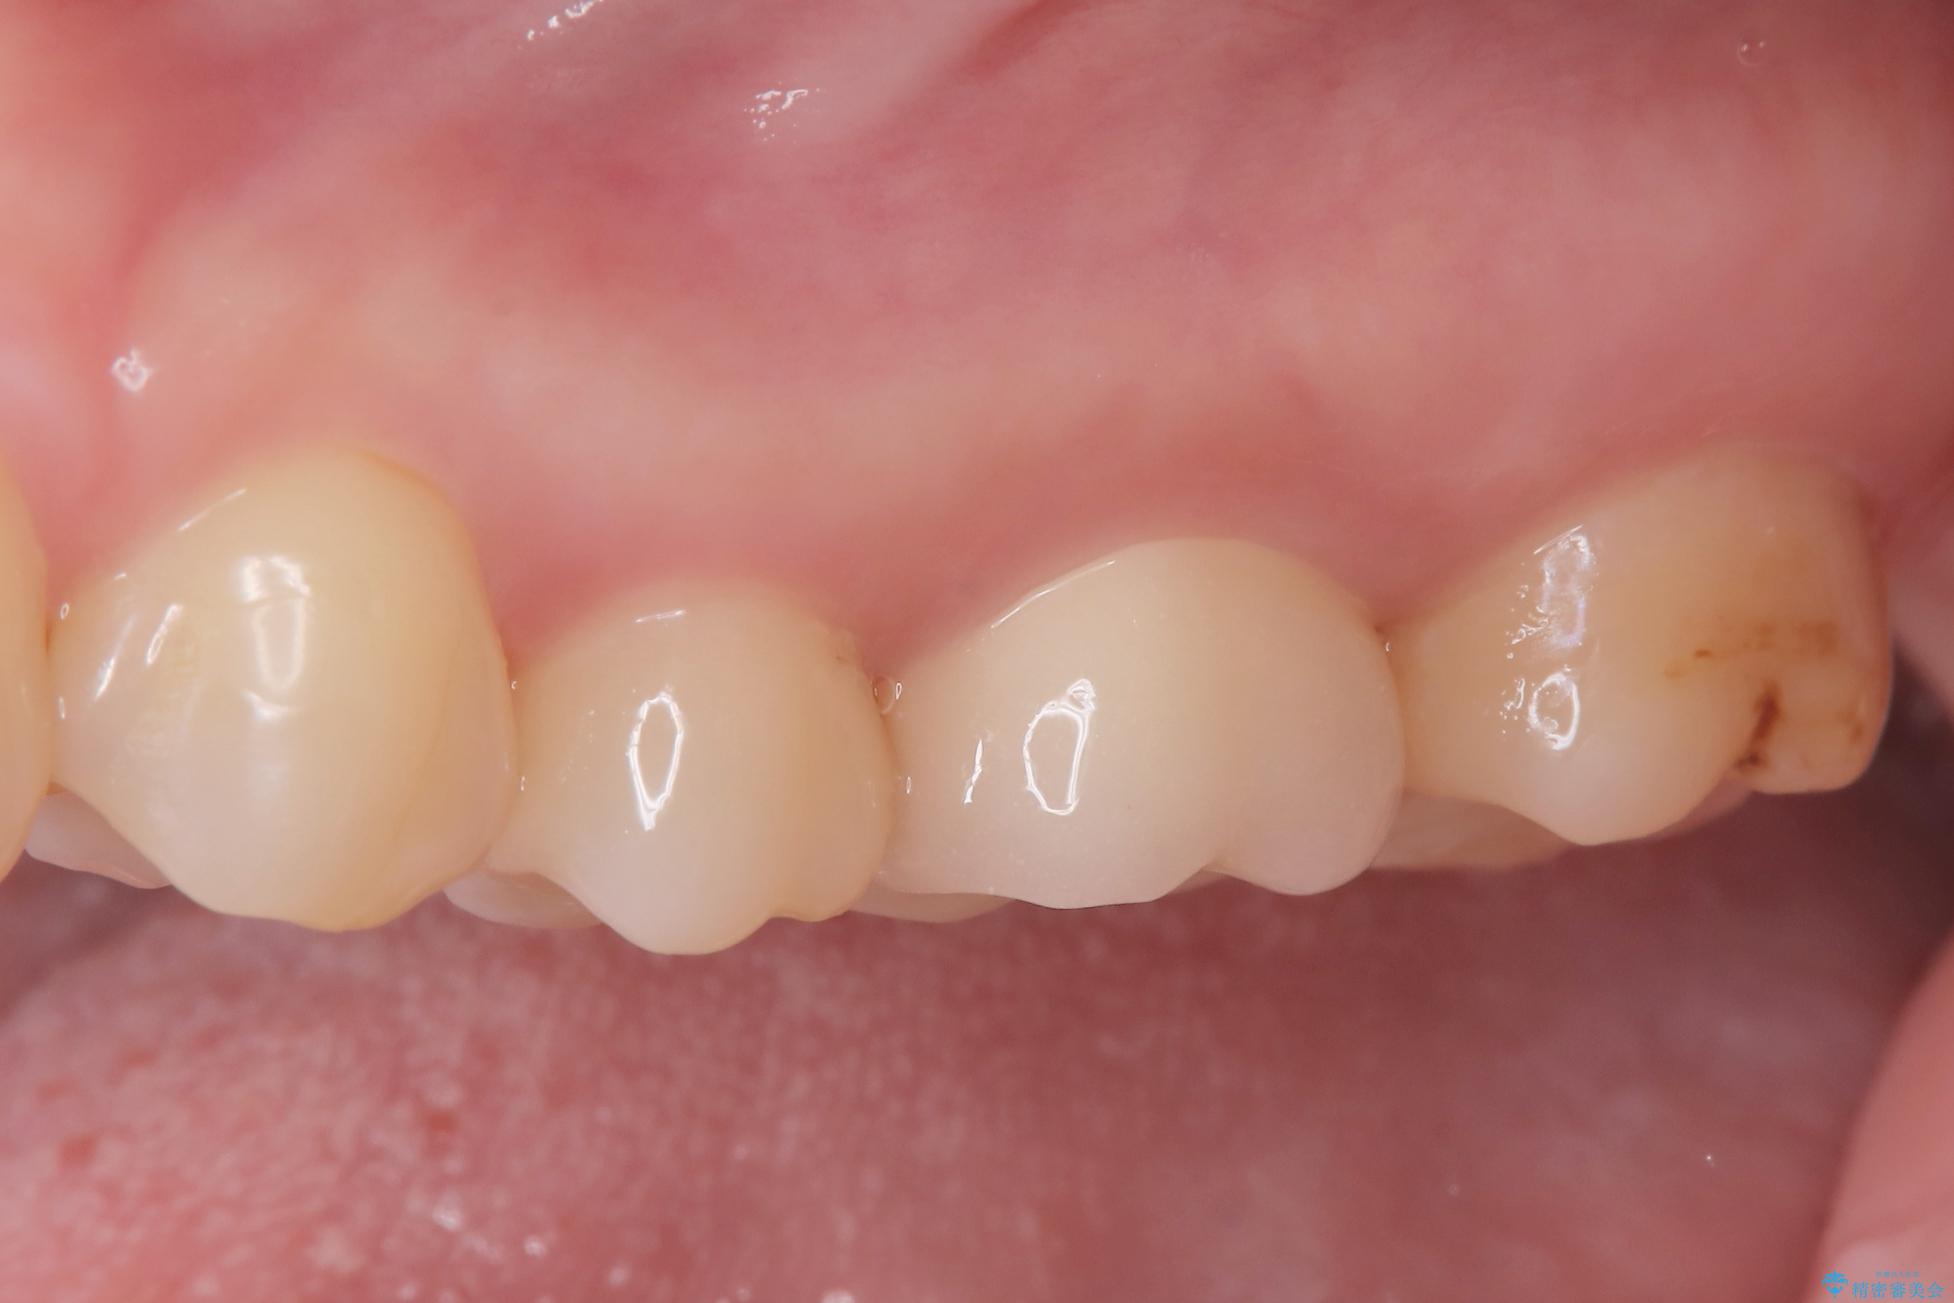

2回で完了した奥歯のセラミック修復

今回の治療では、虫歯の大きさや深さに応じて、異なるセラミック修復法を適用しました。

比較的軽度な虫歯には、セラミックインレー(詰め物)で対応し、健全な歯質を最大限に残しました。

進行した虫歯や歯の強度が低下している歯には、セラミッククラウン(被せ物)を選択し、歯全体を保護することで破折を防ぎました。

短期間での治療を可能にしつつ、天然歯と見分けがつかない審美性と、長期的に安定する機能性を兼ね備えたセラミック修復を実現しました。